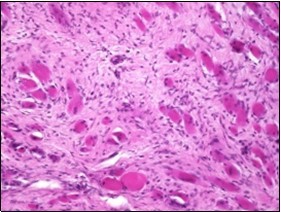

On microscopy, a collagen- rich, minimally cellular, fibrotic soft tissue nodule is exemplified which simulates a scar or conventional fibroma. The neoplasm is comprised of uniform, plump, fibroblastic or myo-fibroblastic cells encompassed in a collagen-rich stroma with infiltration and entrapment of skeletal myocytes 5, 6. Cogent histological examination depicts replacement of muscle fibres and muscle mass with fascicles of fibrous tissue comprised of mature fibroblastic cells, thereby conferring fibrosis 6. Figure 1, Figure 2, Figure 3, Figure 4, Figure 5, Figure 6, Figure 7, Figure 8.

Figure 1.Fibromatosis colli depicting bundles of fibroblasts and myo-fibroblasts intermixed with a collagenous stroma and entrapped myocytes 9.

Figure 2.Fibromatosis colli demonstrating fascicles of fibroblasts and myo-fibroblasts within an abundant collagenous stroma and several mature myocytes 10.